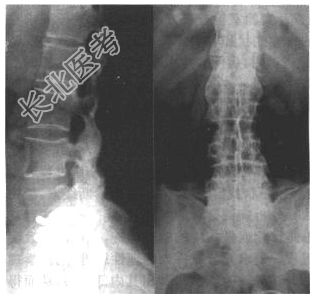

- [材料题] 患者,男,28岁。腰部疼痛不适一年余,脊柱活动受限。血清类风湿因子阴性。X线平片见下图。

- 简答题1、初步诊断为何病?

- 简答题2、AS的诊断依据是什么?